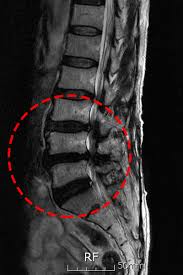

- 영상 검사: X선, MRI, CT와 같은 검사로 척추의 구조적 문제를 확인합니다. 이를 통해 신경이 얼마나 압박받고 있는지에 대한 정보를 제공합니다.